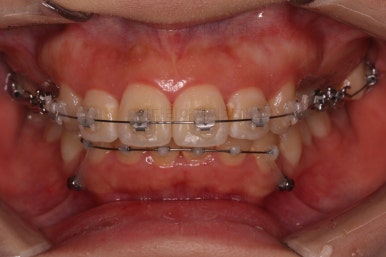

부산무턱교정치과 초진 시 입안의 모습입니다.

전반적으로 치열이 삐뚤고요. 아랫니가 윗니보다 뒤쪽으로 많이 가려져 있죠.

그래서 앞에서 봤을 때 아래 앞니가 거의 보이지 않는 상태인데요.

이런 교합을 "과개교합"이라고 표현합니다.

전반적인 교합, 치열, 과개교합, 튀어나와 보이는 앞니 등을 개선해줘야겠네요.